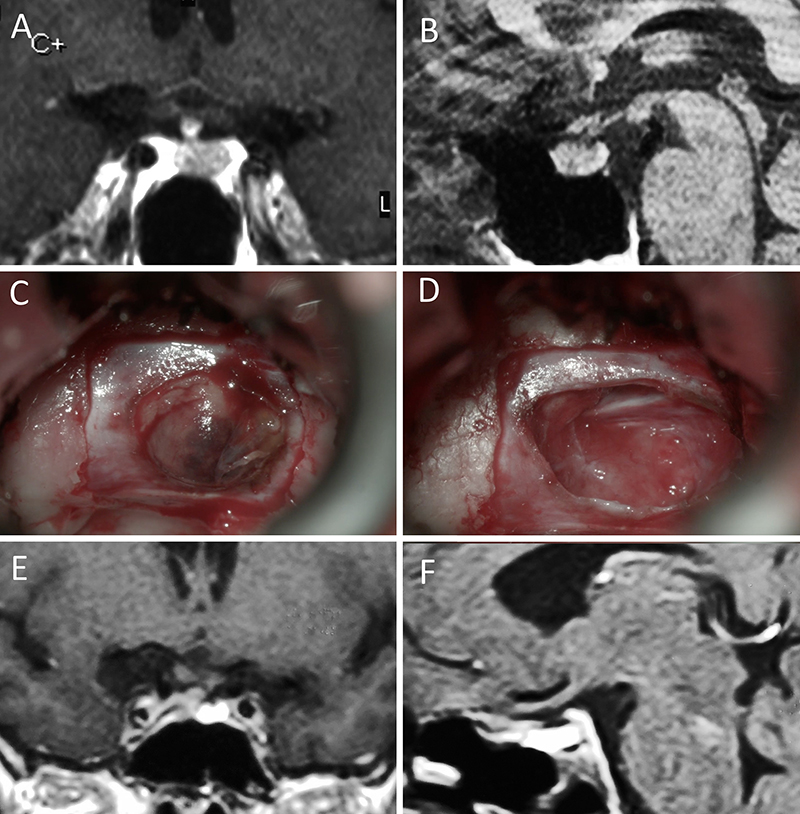

Figura 11: Microadenoma en una mujer de 36 años con Enfermedad de Cushing. Con remisión bioquímica tras la cirugía. A-B: RM preoperatoria; C-D: intraoperatorio; E-F: RM postoperatoria.

Figura 12: Microadenoma en una mujer de 26 años con Enfermedad de Cushing. Con remisión bioquímica tras la cirugía. A-B: RM preoperatoria; C-D: intraoperatorio; E-F: RM postoperatoria.

Figura 13: Macroadenoma en una mujer de 42 años con Enfermedad de Cushing. Con remisión bioquímica tras la cirugía. A-B: RM preoperatoria; C-D: intraoperatorio; E-F: RM postoperatoria.